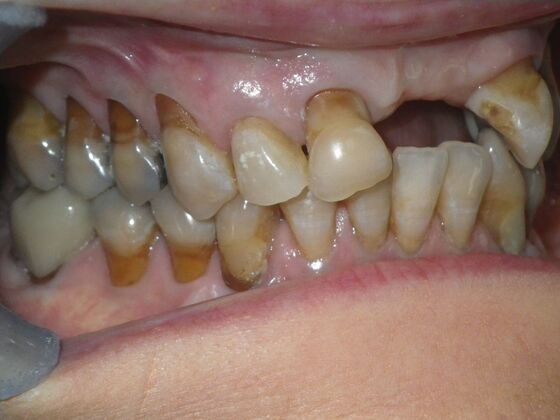

Cosmetic Changes with Veneers and Crown and Bridge: Case 6

Description

This patient had long term acidic erosion of upper and lower teeth eventually leading to loss of upper left central and lateral incisors. While she was somewhat happy with replacement of her front teeth with a removable appliance, she really desired to have something she didn't have to remove. So patient opted to be conservative with two single unit crowns as well as a four unit anterior bridge. These were fabricated using all ceramic without metal